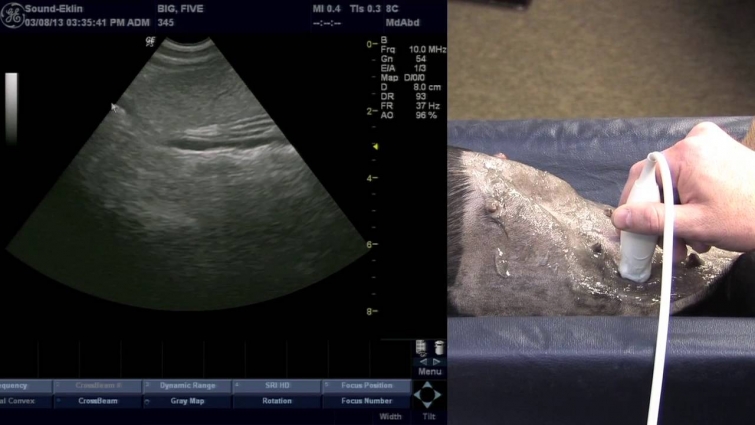

Veterinary Ultrasound Training – Scanning The Spleen

Veterinary Ultrasound Training – Common Spleen Pathologies. Learn common veterinary spleen pathologies in this veterinary ultrasound training video from the …